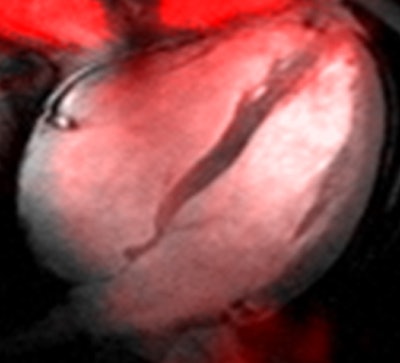

German and Irish researchers have completed what they are calling the first sodium MR images of the heart at 7 tesla to deliver high-resolution images at acceptable scan times, according to just-published research in NMR in Biomedicine.

The 7-tesla acquisitions, facilitated by the use of a customized radiofrequency coil configuration and cardiac gating, achieved isotropic resolution of 6 mm, reported researchers from the Berlin Ultrahigh Field Facility (BUFF) in Berlin, along with co-authors from other institutions including Charité University Medicine in Berlin, the German Cancer Research Center in Berlin, and the University of Dublin.

For sodium MR imaging, standard views of the heart were acquired using a nominal in-plane resolution of 0.5 x 0.5 mm2 and a slice thickness of 15 mm. For whole-heart imaging, the group achieved a nominal 6 mm isotropic spatial resolution via 3D density-adapted sodium MR acquisitions.

"This improvement versus 3D conventional GRE acquisitions reduced partial-volume effects along the slice direction and enabled retrospective image reconstruction of standard or arbitrary views of the heart," Graessi and colleagues reported.

The coil setup showed acceptable radiofrequency characteristics, transmission field homogeneity, and sufficient depth penetration to support sodium imaging of the heart at 7 tesla acquired in clinically acceptable scan times, the authors concluded. The signal-to-noise ratio of the myocardium ranged from 10 to 27 for short-axis views of the heart.

"This achievement supports clear delineation of the myocardium, including deep lying regions of the heart," a goal that was challenging for earlier studies at 3 tesla, the authors added.